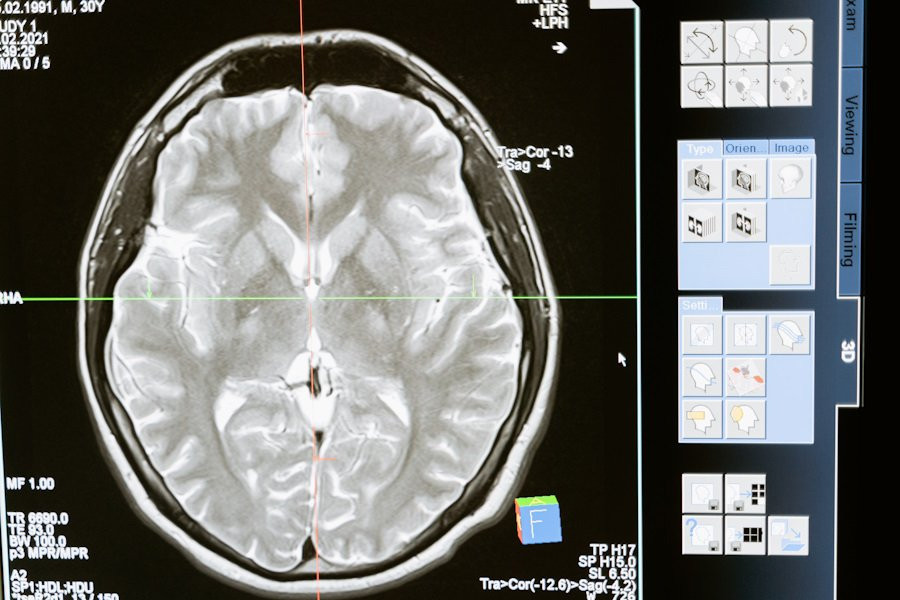

Ученые из Universität Basel (Швейцария) сделали важное открытие, проливающее свет на то, как наша память хранится и изменяется с течением времени. Согласно исследованию, опубликованному в журнале Science, воспоминания о конкретных событиях не сохраняются в мозге в одном экземпляре, как это считалось ранее, а существуют в виде нескольких копий.

Учёные сфокусировались на разных группах нейронов в гиппокампе — области мозга, отвечающей за формирование воспоминаний. Они обнаружили, что когда мозг кодирует новое воспоминание, оно одновременно записывается в нескольких «следах» в этих нейронных группах. Две из таких копий создаются в разных субпопуляциях нейронов: одни из них рождаются на раннем этапе, а другие — позже. Эти нейронные группы активируются и развиваются по-разному после того, как воспоминание было записано.